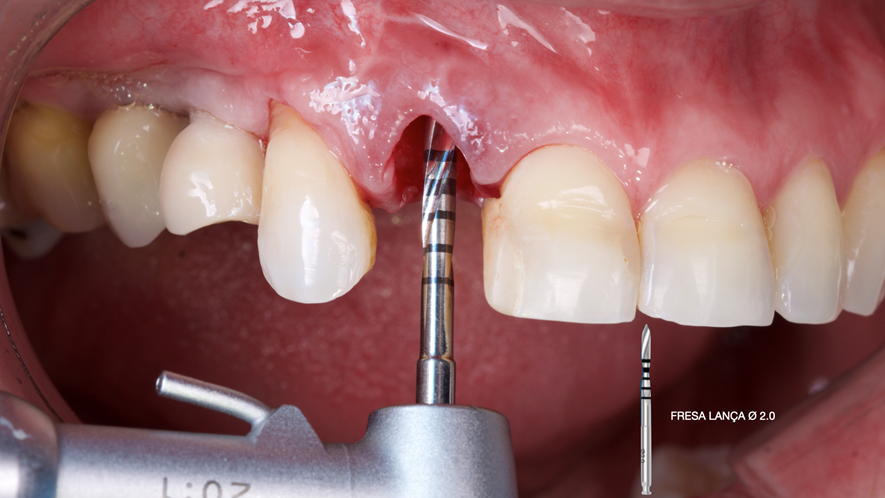

Este trabalho tem como objetivo relatar um caso clínico de exodontia minimamente invasiva de um incisivo lateral superior com fratura radicular, realizando implante imediato em alvéolo pós-extração, enxerto de tecido conjuntivo subepitelial e osso bovino liofilizado para preenchimento de GAP, prontamente à instalação de pilar reto e provisório imediato.